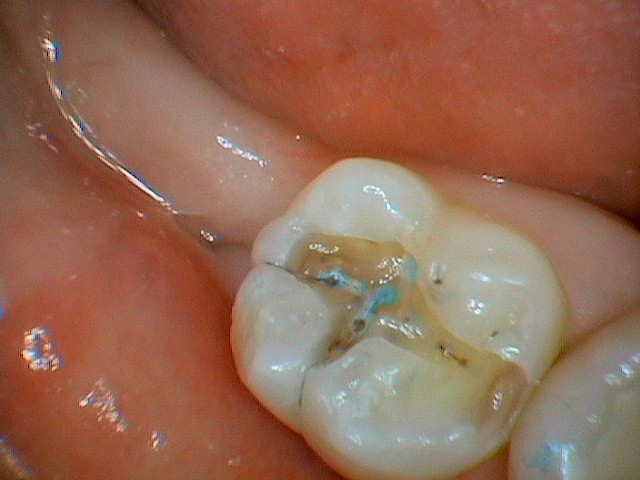

この写真が、治療を始める前の状態です。

見た目では、虫歯には見えないかもしれませんね。

この患者様も、痛みは全くなく、虫歯が見つかりました。

ですが、この歯の中に、大きな「アリの巣」が潜んでいるんです…。

また、当院では、虫歯を残すことがないように、特殊な「う蝕検知液(虫歯を青く染める液)」を使用しています。

虫歯菌に侵された部分は青く染まるので、肉眼では分かりにくい小さな虫歯も見逃さず、徹底的に取り除くことができるんです。

この写真では、もう青く染まっている部分がないのがお分かりいただけると思います。これで、虫歯は全て除去完了です!